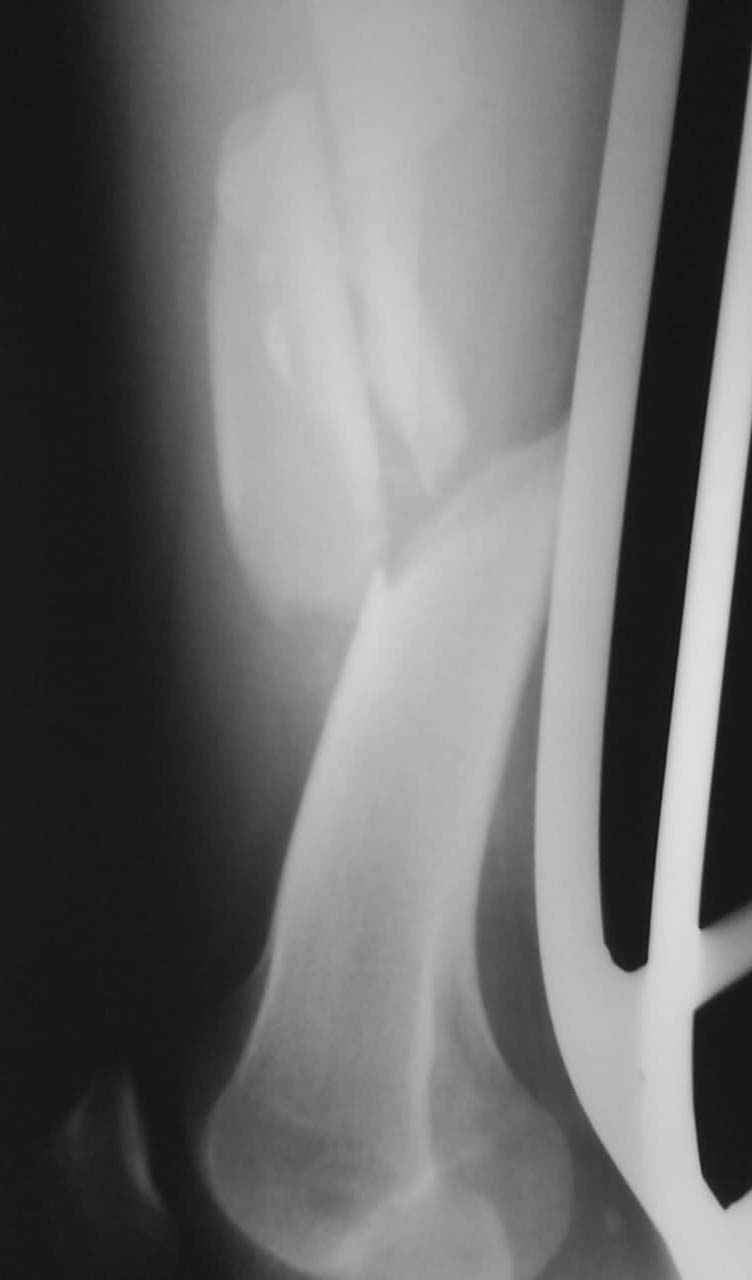

Уважаемые коллеги! От имени Алексея Смирнова всем спасибо за обсуждение. Больной прооперирован. Снимки в приложении.

Мы бы не стали открывать, такие переломы срастаются, хотя бы и с краевым дефектом. То есть если удалять стержень потом, то сильно попозже обычного. В приложении пример. Сразу после операции и через 11 мес. Понятное дело, пациент к тому времени давно и не хромал, и функция колена была полная.

Алексей, привет! Слева поставил бы то же, что и ты планируешь. Справа бы UFN, лучше в экспертном исполнении, или отверстий насверли. DFN можно, конечно, но я бы колено дырявить не стал. Недавно "сделали" такой же перелом UFN-ом, снимки завтра перешлю на почту. Через месяц будут проблемы с репозицией. Не думал справа сначала аппаратом ось исправить, а затем штифтовать?